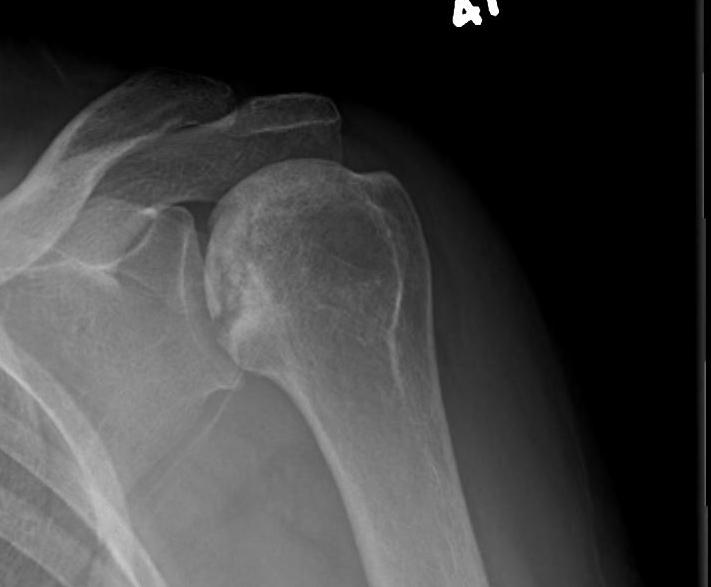

Pathology

Superior head collapse at 90° mark

- area of peak contact stress in abduction

- glenoid rarely affected

- soft tissue and subscapularis rarely contracted

Classification / Cruess modification of Ficat-Arlet

Stage II - sphericity maintained / sclerotic changes in superior central head / crescent sign

Stage III - mild flattening articular surface

Stage IV - significant humeral collapse with loss integrity joint surface

Stage V - degeneration extends to involve glenoid